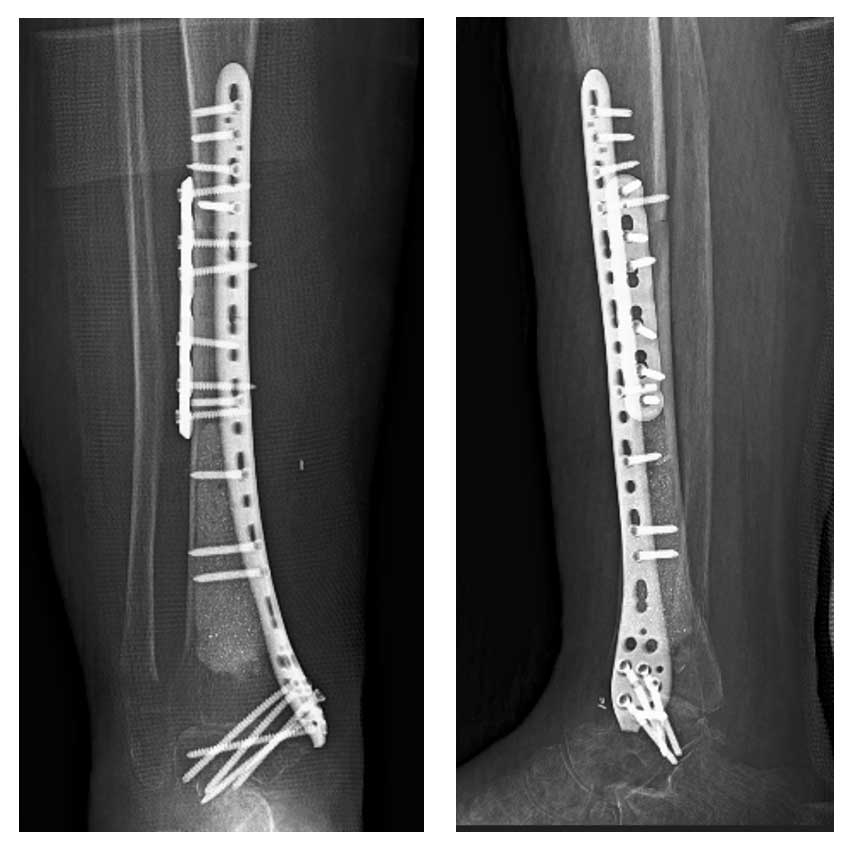

Hastaya geniş rezeksiyon uygulanarak tümörlü kemik dokusu çıkarıldı. Ardından, çıkarılan kemik parçası sıvı azot ile geri kazanım işlemine tabi tutuldu ve yeniden anatomik pozisyonuna yerleştirilerek fiksasyon sağlandı. Bu yöntem, hem biyolojik bütünlüğü koruma hem de ekstremite fonksiyonlarını sürdürme açısından tercih edilmiştir.

Ameliyat sonrası dönemde hastada komplikasyon gelişmemiştir. Fonksiyonel sonuçlar başarılı olup, hasta yara iyileşmesini takiben onkolojik ve fizik tedavi sürecine yönlendirilmiştir.

Ameliyat Sonrası: Geri kazanılan distal tibianın fiksasyonu görülmekte.